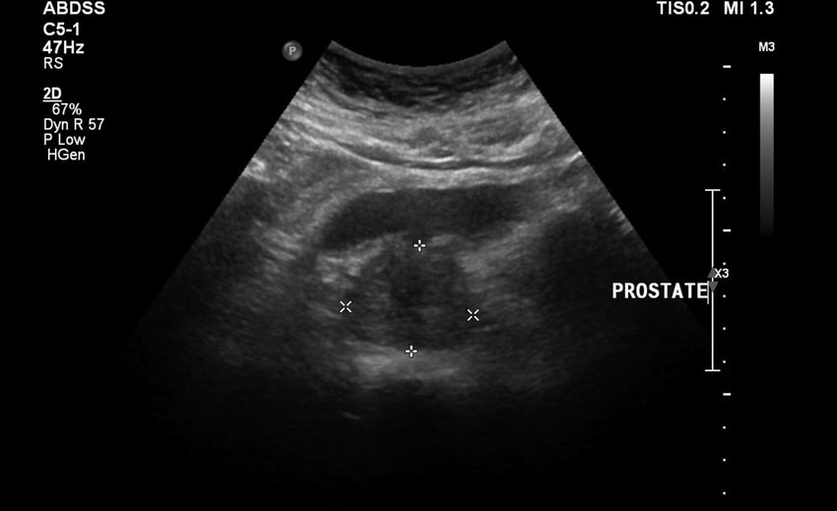

They did not let the rubberized live calmly, so back pain was added, the tests and results of the ultrasound were bad.It was literally impossible to get away from the bathroom, there was a feeling of heaviness in the groin and constant pain.The direct prostate massage was prescribed, which immersed me in panic.He started looking for other less traumatic treatment methods.